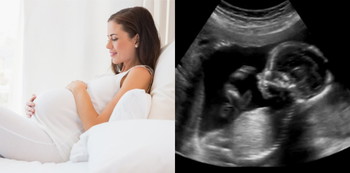

Perkembangan Bayi Semasa Kehamilan Minggu Ke 17

Bayi anda sedang membesar dengan baik dan kini sebesar saiz lobak putih (turnip).

Ketika kandungan 17 minggu, janin telah mencapai saiz kira-kira 13 sentimeter dan berat kira-kira 140 gram.

- Denyutan Jantung Janin: Doktor mungkin menggunakan Doppler atau peranti lain untuk memeriksa degupan jantung janin dan memastikan kesihatannya.

- Pemeriksaan Saiz Rahim dari Luar: Saiz rahim akan diukur dari luar untuk menentukan pertumbuhan janin dan memastikan semuanya berjalan mengikut perancangan.